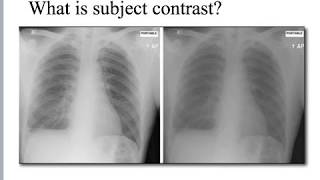

X Ray Subject Contrast Youtube